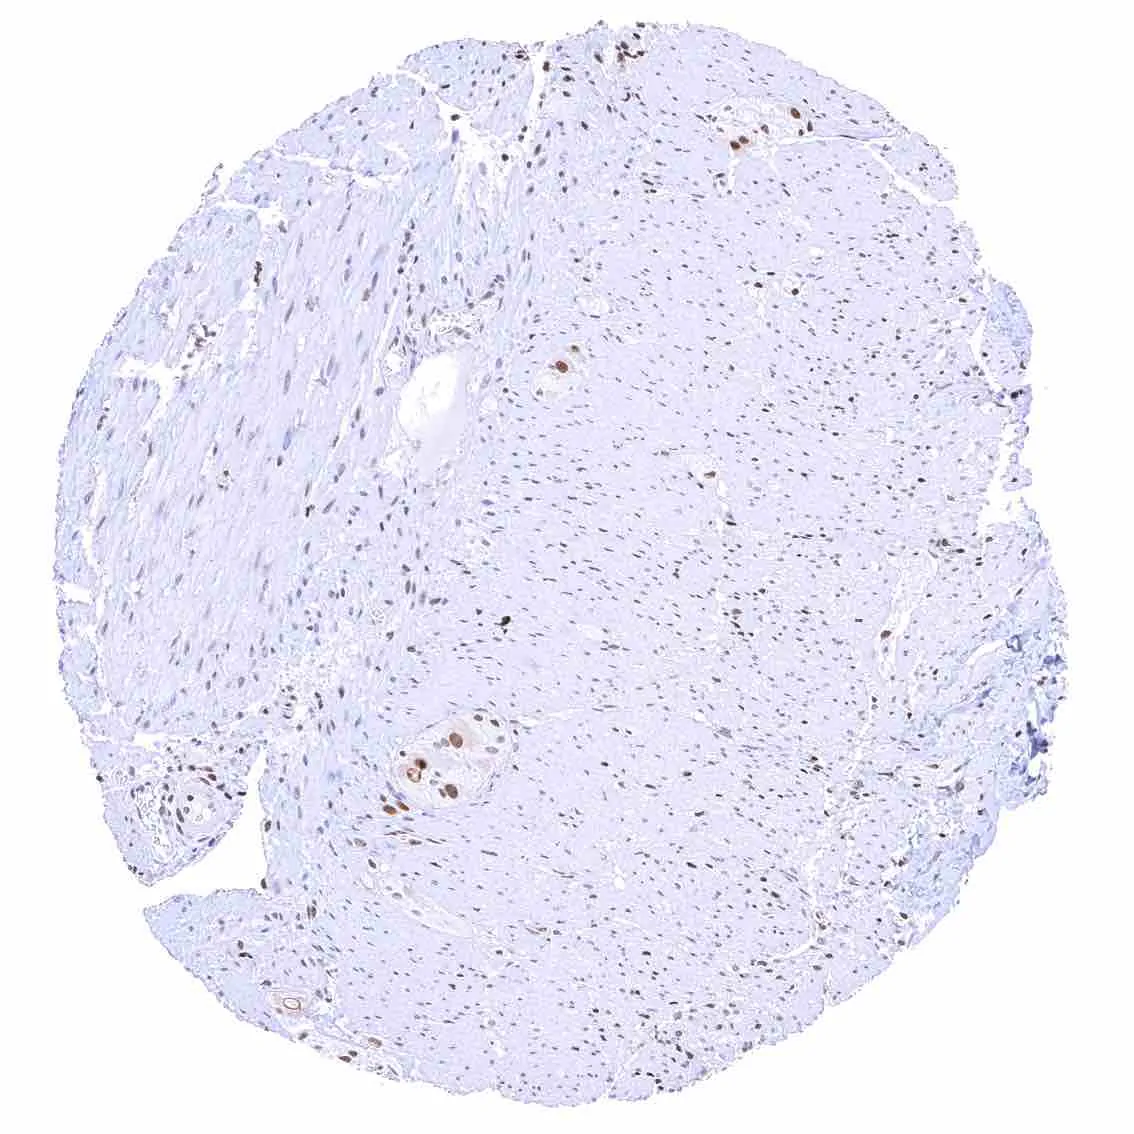

Heart muscle – Distinct nuclear p27 staining of stroma cells while myocytes are largely negative.